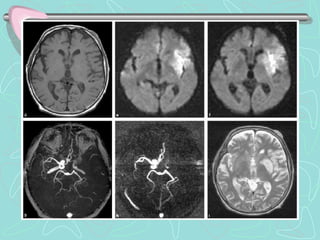

RESONANCIA MAGNETICA

•Útil en Ictus Isquémico Agudo, menor de 6h, con mejor sensibilidad

que TC

•RMN secuencia de Difusión y Perfusión, para menores de 3 horas

•No útil en Ictus hemorrágico agudo

ARTERIOGRAFÍA DE CAROTIDAS

•Técnica invasiva, con uso de contraste

•Detecta obstrucción de vasos sanguíneos (Ictus isquémico)